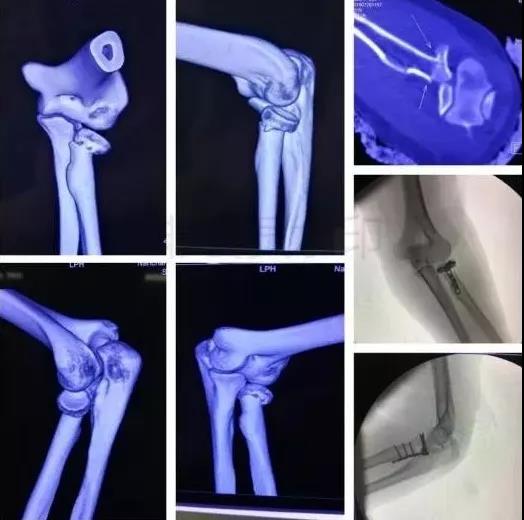

3)肱骨远端骨折

- 骨筋膜室综合征,立即减压。

- 前臂三大神经,肘血管损伤均可以探查。

4)复杂肘关节骨折(尺骨鹰嘴,桡骨头)

- 伤后1周内手术

- 2周后手术-骨化性肌炎

- 术后尽量不要肘关节制动,制动不超过2周。